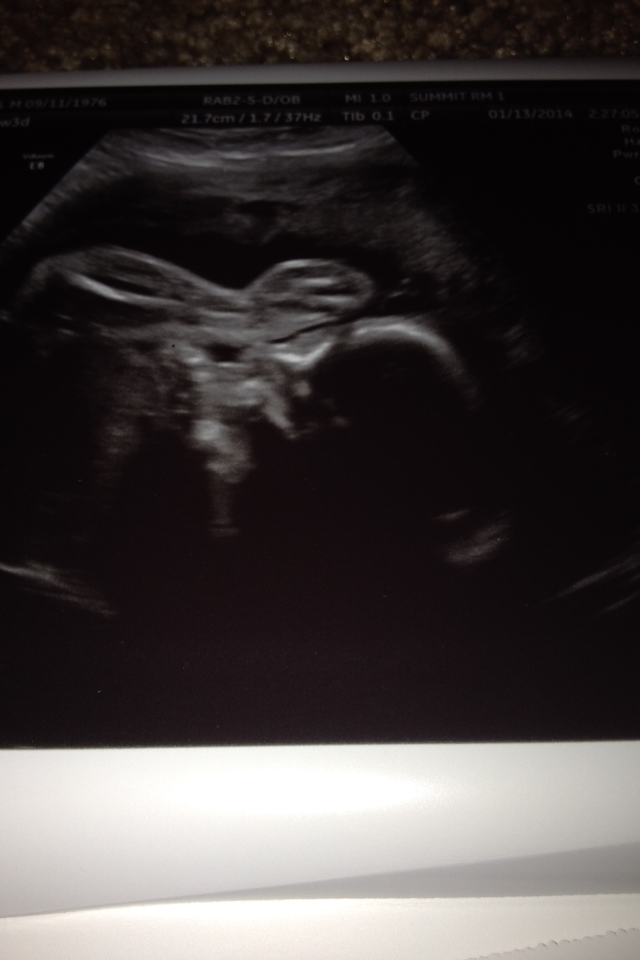

Of course we had picture time today and he cooperated-somewhat! Baby was head down, but he had his feet all the way on his head. After a couple of tries, we were able to get a picture that showed his face and foot. The tech said he is very flexible! While she was figuring out his position, she quickly moved and asked if we knew his gender. We said yes. She said good and then moved back to where she was and said because he wasn't hiding anything today!